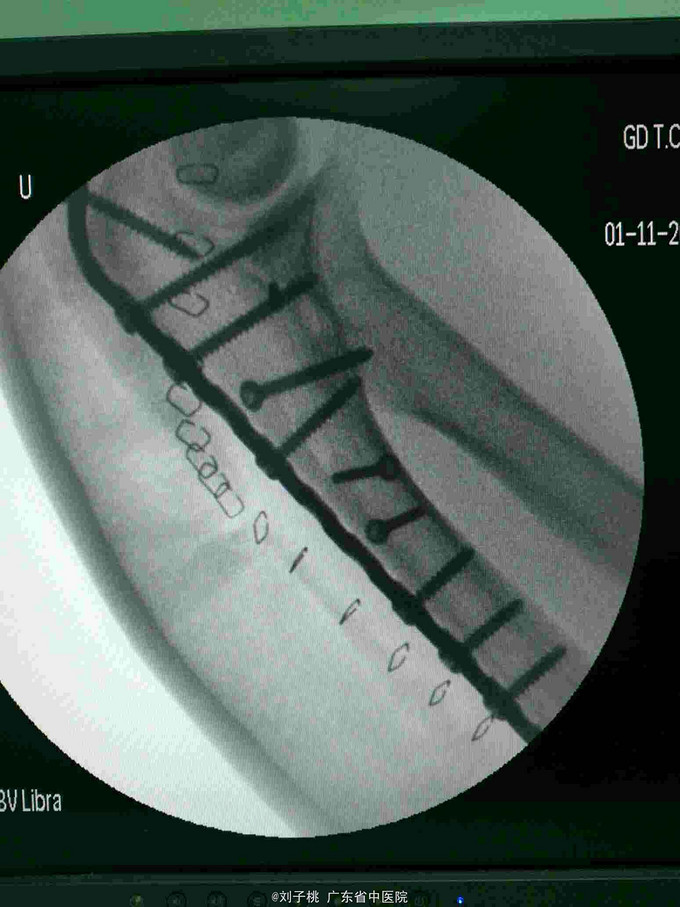

#骨科科室play#右肘开放性孟氏骨折

右肘开放性孟氏骨折,尺神经断裂,急诊行清创内固定加神经修复。